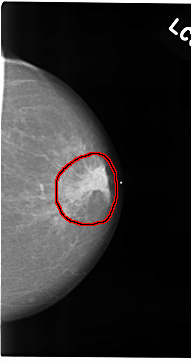

C_0074_1.LEFT_CC

LEFT_CC LINES 4704 PIXELS_PER_LINE 2472 BITS_PER_PIXEL 12 RESOLUTION 50 OVERLAY

FILE: C_0074_1.LEFT_CC.OVERLAY

TOTAL_ABNORMALITIES 1

ABNORMALITY 1

LESION_TYPE MASS SHAPE IRREGULAR MARGINS SPICULATED

ASSESSMENT 5

SUBTLETY 5

PATHOLOGY MALIGNANT

TOTAL_OUTLINES 1

BOUNDARY